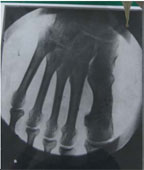

乃木希典大将左足X線写真は、明治38(1905)年にドイツから輸入し広島倫治病院に設置されたX線装置を用い、明治39(1906)年1月11日、乃木希典大将が西南戦争時に負傷した左足のX線写真を撮影したものである。

乃木希典大将左足X線写真